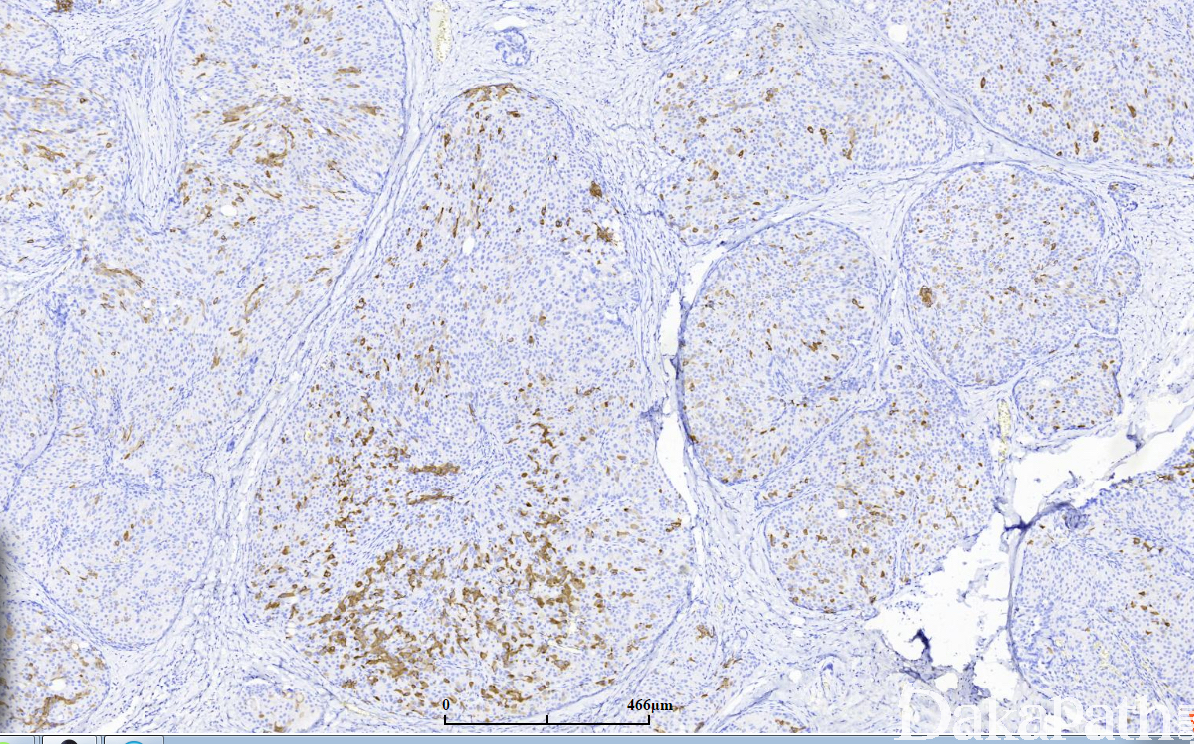

免疫组织化学染色:

50-60%病例表达突触素(Syn)和/或嗜铬素(CgA)等神经内分泌标记;上皮细胞一般不表达高分子量角蛋白(CK5/6),肌上皮细胞免疫标记物(p63. 平滑肌肌球蛋白重链、calponin 等)可以证实实性乳头状癌中间和周围都没有肌上皮细胞的存在。